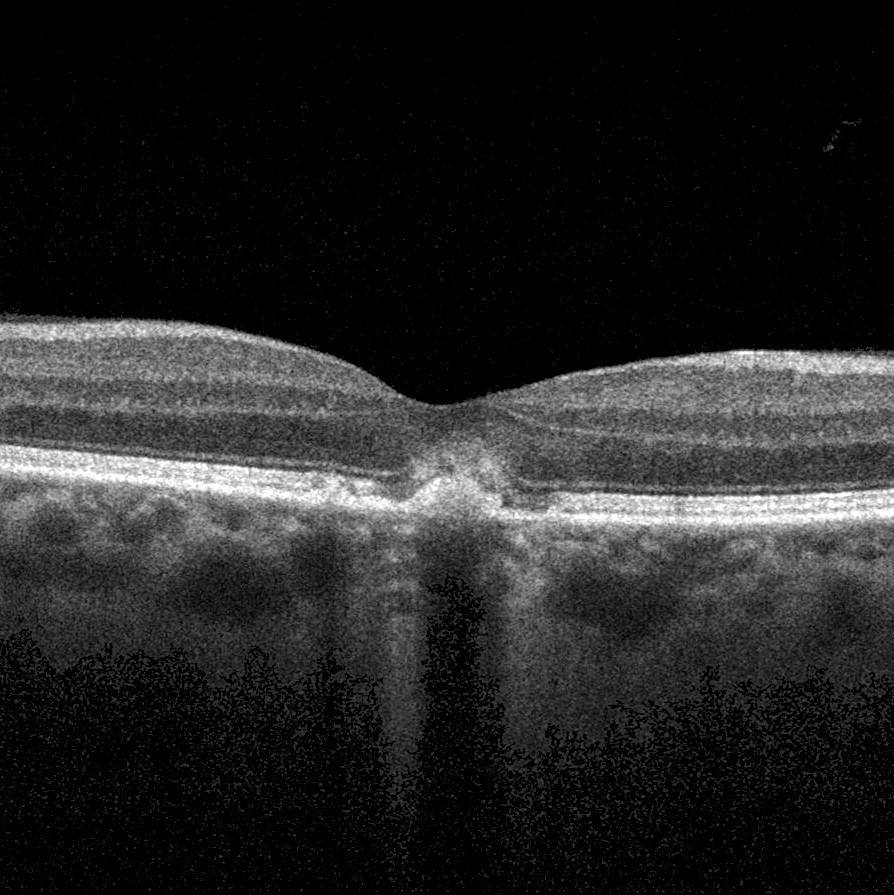

AVD_OCT_edited

Full size 894 × 895